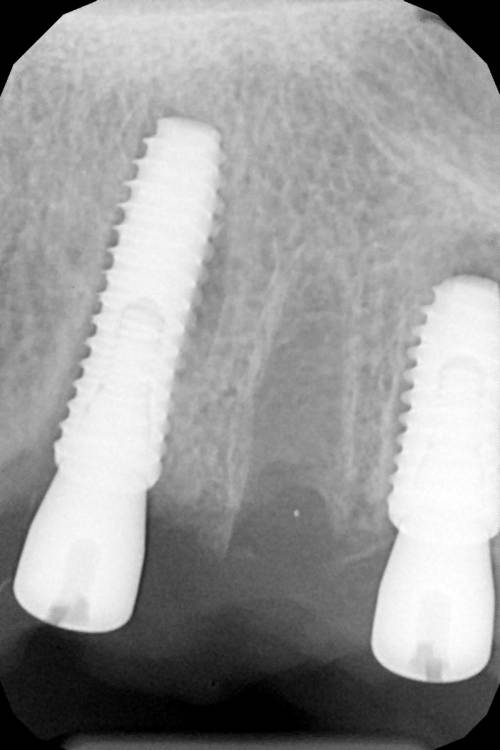

Женька Опубликовано 19 апреля, 2021 Автор Поделиться Опубликовано 19 апреля, 2021 Rg Ссылка на комментарий

Женька Опубликовано 21 июля, 2021 Автор Поделиться Опубликовано 21 июля, 2021 3 месяца минуло... клык на торке 30 неприятные ощущения второй премоляр на 10 и подвижность... отправил на кт. Всё насмарку... Ссылка на комментарий

Борис80 Опубликовано 21 июля, 2021 Поделиться Опубликовано 21 июля, 2021 премоляр в любом случае недозаглубитом болеет... Ссылка на комментарий

Женька Опубликовано 2 августа, 2021 Автор Поделиться Опубликовано 2 августа, 2021 2.5 с тупым перкуторным звуком И вишенка, нет АРБУЗИЩЕ, на торте 2.3 в соседней теме в ортопедии посоветовали перестать уничтожать людям зубы, тоже самое помоему можно сказать и по хирургии... Правильно же понимаю, что протезировать такой (2.3) не стоит. Даже если торк выдержит в 35 чревато проблемами после установки постоянной ортопедии. Ссылка на комментарий